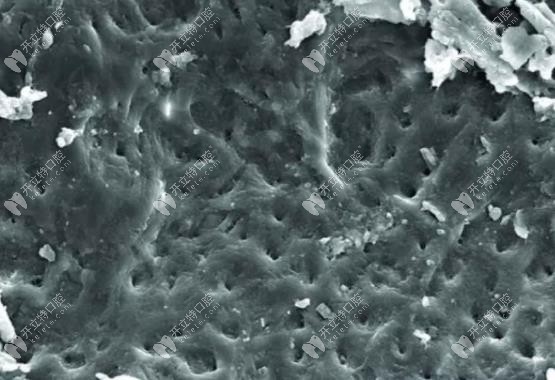

沒有沖洗過的根管鈣化外觀

▲▲未經(jīng)過EDTA藥物沖洗的根管鈣化外觀▲▲